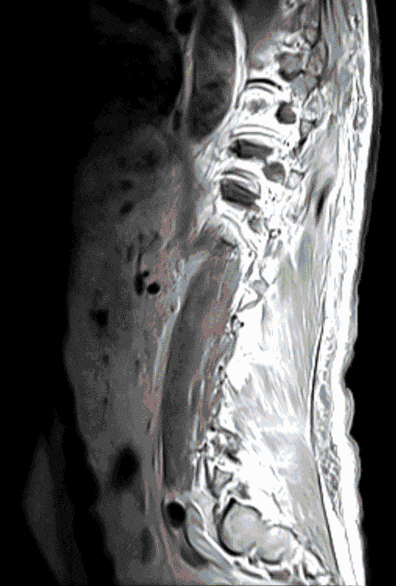

In approximately 5% of all cancer patients (e.g. patients with lung, prostate or breast cancer), the spine is affected by metastases. Metastases can endanger the stability of the spine or lead to pain and neurological dysfunction due to pressure on the spinal cord and nerves.

Therapy is carried out in close interdisciplinary cooperation with oncological and radiotherapeutic colleagues (tumor board). Various surgical therapies can maintain/restore stability, relieve spinal cord compression and alleviate pain.